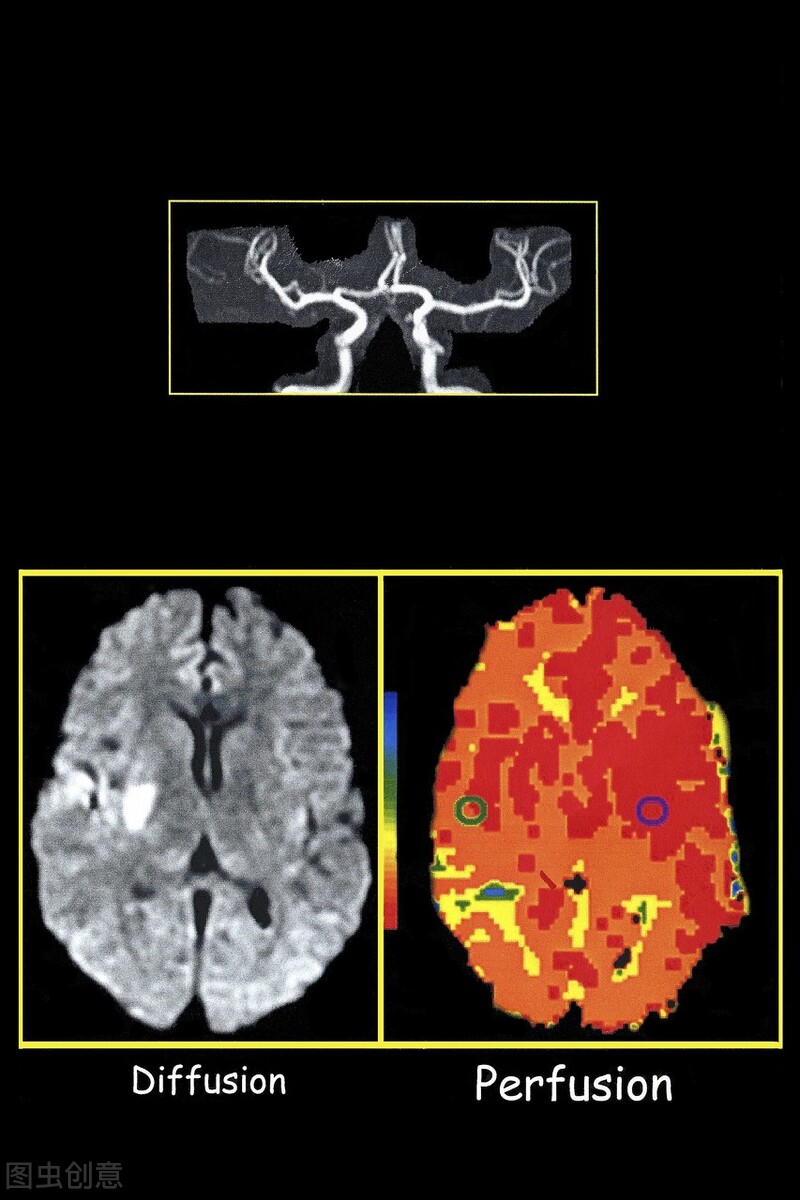

2. 烟雾病 烟雾病有不到半数的患者合并无症状性 脑微出血,多见于脑室旁白质、颞叶皮层、基底节区,提示这些血管比较脆弱,发生了扩张,可能是未来出血的标志。建议脑血管检查,例如脑血管造影术。